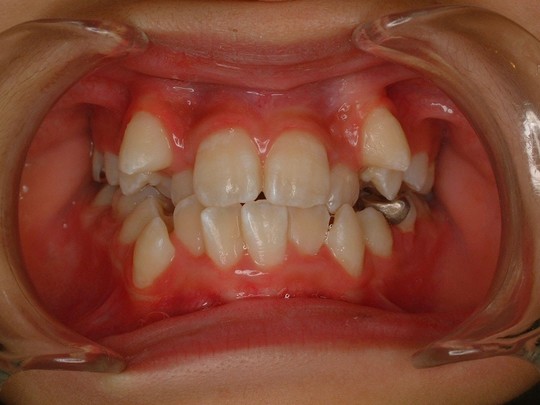

治療後

上下の歯並びが綺麗に並びました。

お口の模型とレントゲン写真をもとにした術前診査から、上下の顎の成長が弱く、歯の大きさに対して顎が小さいため、本来並ぶべき場所に歯が並ぶことができないために歯列不正が生じていることがわかりました。治療内容としては、年齢的に顎の成長がほぼ終了していることから、上下小臼歯の抜歯を行って歯がきれいに並ぶためのスペースを作り、ブラケットを使用して治療を行いました。